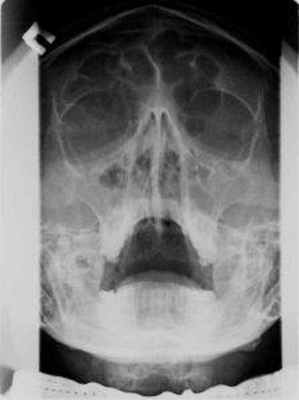

Чаще встречающаяся катаральная форма острого гайморита ведет к отеку слизистой оболочки и значительному увеличению ее толщины, что находит свое выражение в характерных рентгенологических симптомах. На типичной рентгенограмме в подбородочно-носовой проекции при наклонном положении головы больного обнаруживается незначительное понижение воздушности пазухи и характерное краевое затемнение, обычно одинаковой ширины на всем протяжении, с резкими контурами.

Такое краевое затемнение обусловлено отечной слизистой оболочкой. Таким образом, до того момента, пока существует центральное просветление пазух, т. е. полость, не занятая отечной тканью, диагноз катаральной формы острого гайморита может быть установлен рентгенологически.

Если процесс прогрессирует, отечная слизистая оболочка может полностью закрыть просвет пазух, что приводит к исчезновению рентгеновского изображения краевой тени и появлению симптома сплошного затемнения. Сплошное затемнение гайморовой пазухи теряет значение прямого признака, так как оно обнаруживается и при наличии жидкости в пазухе в случае эксудативной формы гайморита.

При клинических указаниях на острую эмпиему гайморовой пазухи с целью получения симптома уровня жидкости в пазухе рентгенография производится в той же проекции при вертикальном положении головы и кассеты. Этот прямой диагностический симптом бывает особенно хорошо выражен в той фазе острой эмпиемы, когда слизистая оболочка сохраняет почти нормальную толщину при резко выраженном выделении жидкости.

Если же рентгенография происходит в тот период, когда слизистая оболочка достигает значительной толщины, условия для получения на рентгенограмме симптома уровня жидкости становятся неблагоприятными. Мы обратили внимание на симптом, который при условиях краевого затемнения позволяет с большой долей вероятности предполагать скопление жидкости в пазухе при уменьшении ее просвета отечной слизистой оболочкой.

Признак этот заключается в том, что па снимке в подбородочно-носовой проекции при наклонном положении головы больного просвет пазухи, окруженный краевой тенью утолщенной слизистой оболочки, в значительной мере затемнен и не кажется в такой степени прозрачным, как это наблюдается при отеке слизистой оболочки и отсутствии жидкости в остаточной полости. В ряде случаев этот симптом был проверен нами последующей рентгенографией при вертикальном положении головы и кассеты, которая обнаруживала уровень жидкости в пазухе.